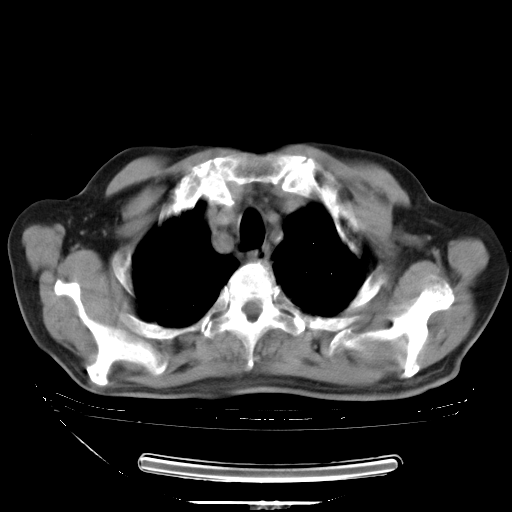

胸腹部CT,诊断意见:左上肺叶钙化灶、左侧胸膜局限性增厚并钙化、胆囊炎。描述部分肺组织呈磨玻璃样改变。